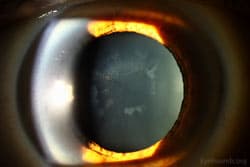

A rare inherited disorder that causes too much copper to accumulate in your vital organs, primarily the liver and brain. A characteristic sign of Wilson disease is the Kayser-Fleischer ring, a rusty-brown ring of copper deposits around the edge of the cornea.

Clinical Images

High-resolution clinical photographs showing various presentations of wilson disease.

- Kayser-Fleischer rings (visible on a slit lamp exam).

- A 'sunflower' cataract may also be present.